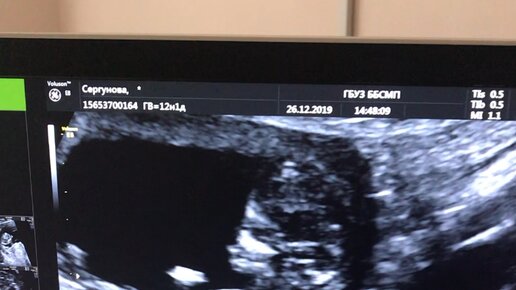

Нормы УЗИ скрининга на 12 неделе беременности

УЗИ скрининг на 12 неделе в период беременности – диагностика, которая дает информацию о том, как развивается плод и все его жизненно необходимые органы. Это исследование показывает, нет ли у плода генетических или хромосомных аномалий. На 12 неделе УЗИ проводится двумя способами на усмотрение врача: трансабдоминально и трансвагинально. Зачем делают процедуру? Первое УЗИ на 12 неделе беременности помогает врачу увидеть все процессы, которые происходят в матке, показывает, как происходит развитие плода, его органов и тканей, нет ли каких-либо дефектов или отхождений от нормы...